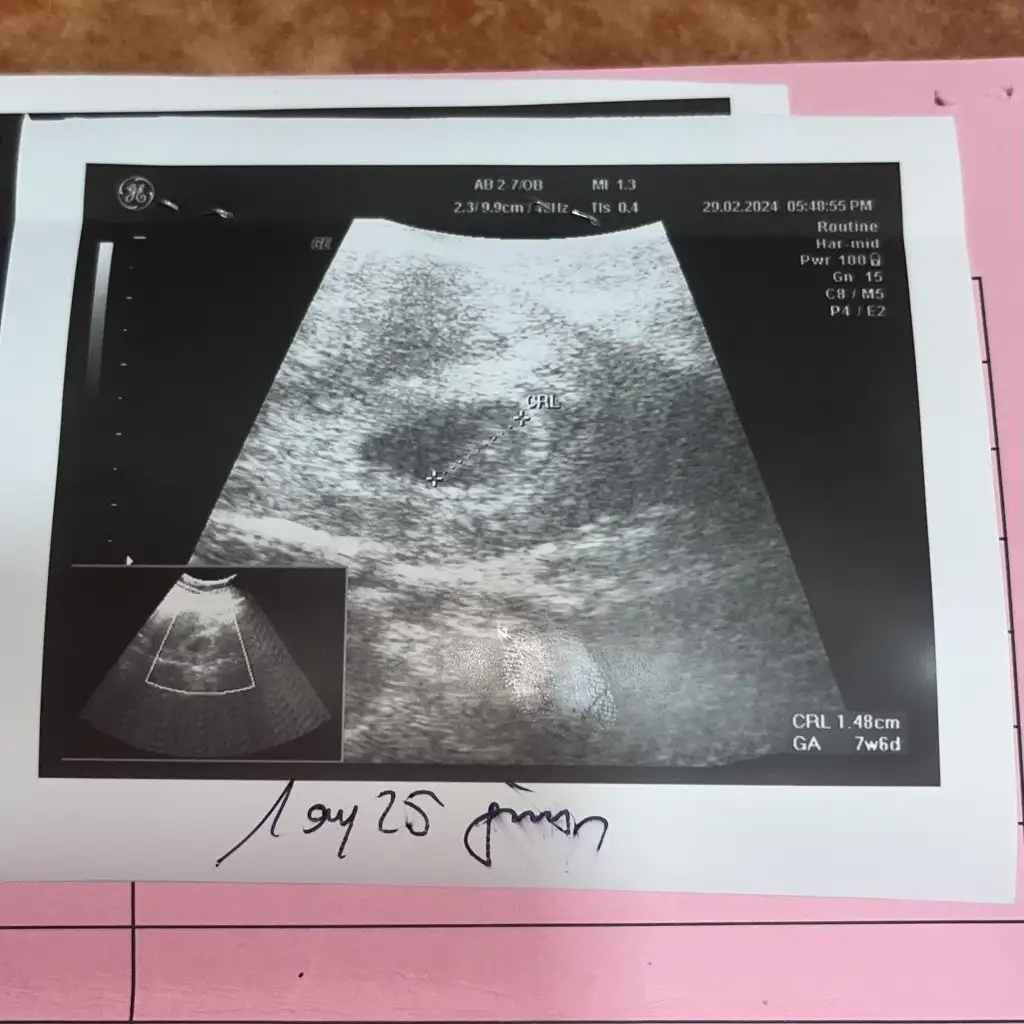

Z zeynep bl Yeni Üye Anneler Kulübü Kayıtlı Üye 1 Mart 2024 1 0 1 29 1 Mart 2024 Konu Sahibi Konu Sahibi ece0519 #43 ece0519 .!.: Merhaba kızlar ultrason görüntüsüne göre cinsiyet tahmini yapabilen var mı? 9 haftalık Kızlar 11 haftalıkki ultrason resmini de ekledimBelki daha net söyleyebilirsiniz. Genişletmek için tıkla... Merhaba benim 8 haftaya yakın şuan. Tahmin edebilecek varmı rica etsem Eklentiler IMG_3991.webp 46,5 KB · Görüntüleme: 60

ece0519 .!.: Merhaba kızlar ultrason görüntüsüne göre cinsiyet tahmini yapabilen var mı? 9 haftalık Kızlar 11 haftalıkki ultrason resmini de ekledimBelki daha net söyleyebilirsiniz. Genişletmek için tıkla... Merhaba benim 8 haftaya yakın şuan. Tahmin edebilecek varmı rica etsem